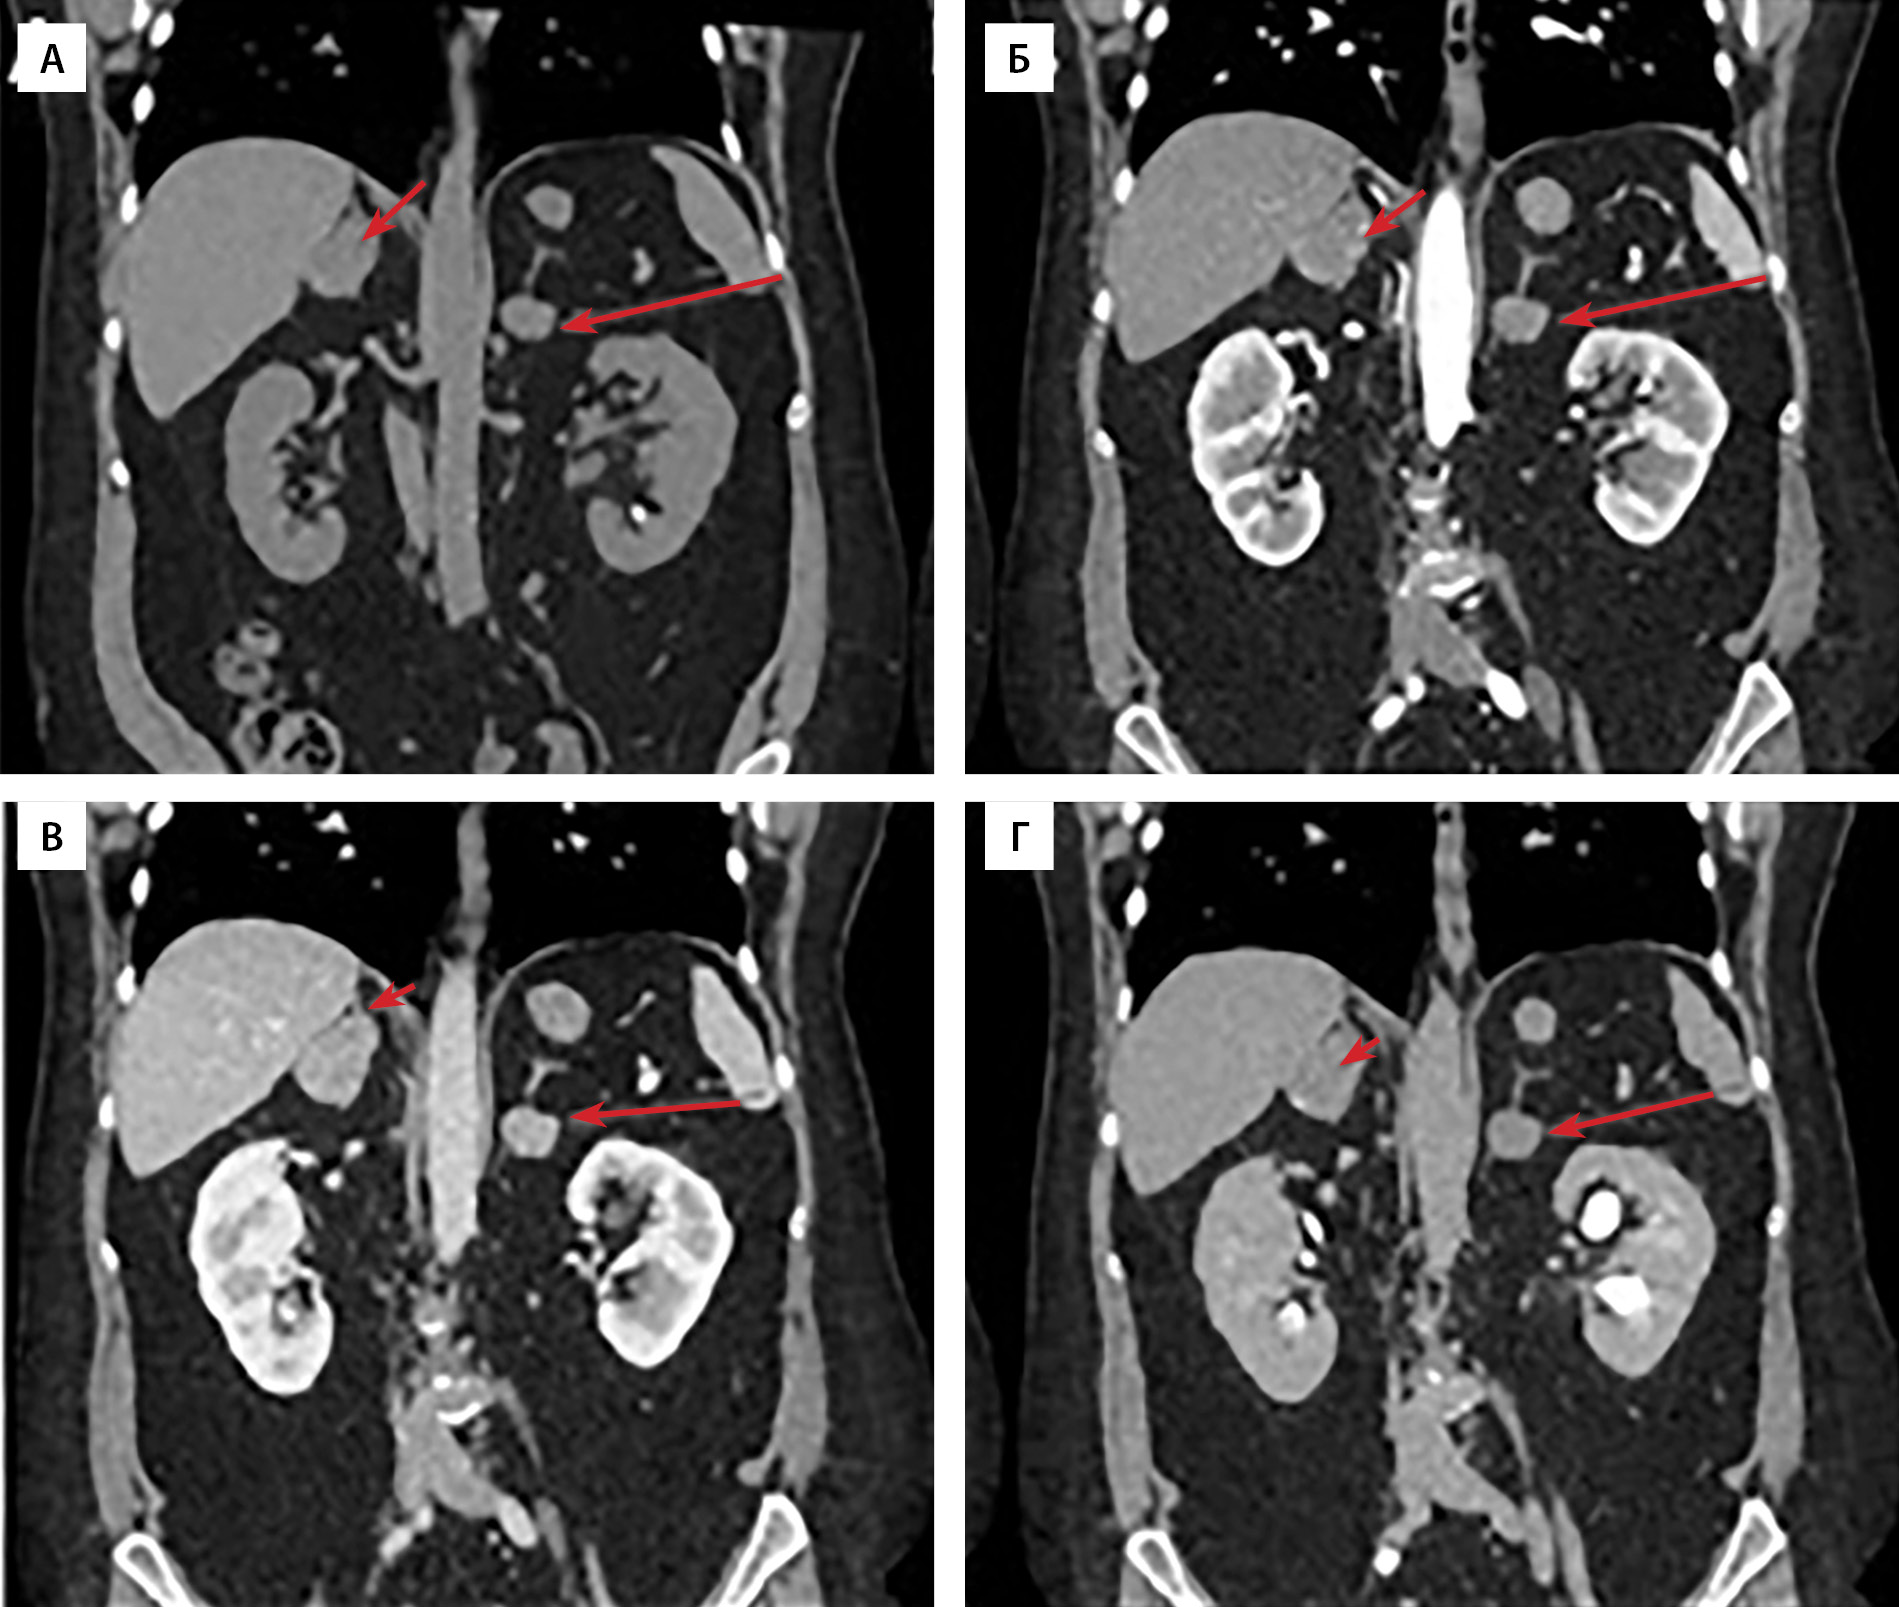

По данным мультиспиральной компьютерной томографии (МСКТ) надпочечников: образование левого надпочечника бобовидной формы с четкими ровными контурами, однородной структуры, размерами 25×14×20 мм. При болюсном контрастном усилении образование неоднородно накапливает контрастный препарат, максимально в венозную фазу. Плотность его по фазам составляет (нативная-артериальная-портальная-отсроченная): 50–59–106–54 ед.Н. Вымывание контрастного препарата: абсолютное 92,9%, относительное — 49,1%. Регионарные лимфатические узлы не увеличены. Образование правого надпочечника овальной формы с четкими бугристыми контурами, неоднородной структуры, размерами 29×41×35 мм. В структуре определяются кальцинаты. При болюсном контрастном усилении образование неоднородно накапливает контрастный препарат, максимально в венозную фазу. Плотность по фазам составляет (нативная-артериальная-портальная-отсроченная): 46–55–104–52 ед.Н. Вымывание контрастного препарата: абсолютное 89,7%, относительное — 50%. В артериальную фазу в структуре обоих образований определяются мелкие гиперконтрастные включения плотностью до 188 ед.Н. Регионарные лимфатические узлы не увеличены (рис. 1, 2, 3). По заключению — образования обоих надпочечников необходимо дифференцировать между атипичными аденомами с низким содержанием жира и образованиями злокачественной природы.

Рисунок 3. Мультиспиральная компьютерная томография образований обоих надпочечников, корональная проекция: А — нативная фаза; Б — артериальная фаза; В — портальная фаза; Г — отсроченная фаза. Образование правого надпочечника (короткая стрелка), левого надпочечника (длинная стрелка).

5. Рисунок 3. Мультиспиральная компьютерная томография образований обоих надпочечников, корональная проекция: А — нативная фаза; Б — артериальная фаза; В — портальная фаза; Г — отсроченная фаза. Образование правого надпочечника (короткая стрелка), левого надпочечника (длинная стрелка). | |